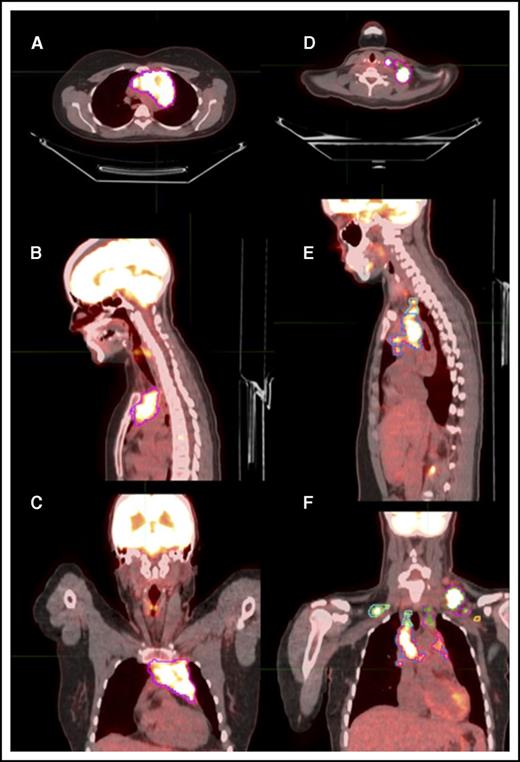

After image reconstruction, PET-CT images were transferred to MIM software, version 6.4.9 (MIM Software Inc, Cleveland, OH), and fused for further analysis. All SUV measurements reported in this work are based on patient body weight. Because no universal consensus has been reached on how to define MTV, we measured MTV on the initial PET-CT scans using a threshold method restricted to areas of disease with SUV ≥2.5 (MTV extracted from threshold volumes [MTVt]).9 To account for areas of tumor that might not have significant uptake because of necrosis or other causes, we devised the soft-tissue method, in which the soft-tissue nodes or masses showing any SUV uptake were contoured and the 3D volume in cubic centimeters was designated as the MTVst. TLG extracted from threshold volumes (TLGt) or TLG manually contoured soft-tissue volumes (TLGst) was calculated as mean SUV in the contoured regions × the corresponding MTV. Representative contours from both methods of delineation are presented in Figure 1. The diameter of the longest nodal mass or conglomerate was measured for each patient in the axial, sagittal, and coronal dimensions.

Representative delineation of MTV based on both the MTVst and MTVt contouring methods. Axial, sagittal, and coronal sections might not show the same node but rather different regions of disease in each anatomical section. (A-C) Axial, sagittal, and coronal scans of mediastinal disease contoured based on MTVst (magenta) and MTVt (blue) methods. (D) Axial view of left cervical neck disease contoured based on MTVst (magenta) and MTVt (green) methods. (E) Sagittal view of left cervical neck disease contoured based on MTVst (magenta) and MTVt (green) methods and mediastinal disease contoured based on MTVst (blue) and MTVt (pink) methods. (F) Coronal view of left cervical neck disease contoured based on MTVst (magenta) and MTVt (green) methods, mediastinal disease contoured based on MTVst (blue) and MTVt (pink) methods, left axillary disease contoured based on MTVst (yellow) and MTVt (brown) methods, and right cervical neck disease contoured based on MTVst (light blue) and MTVt (light green) methods.